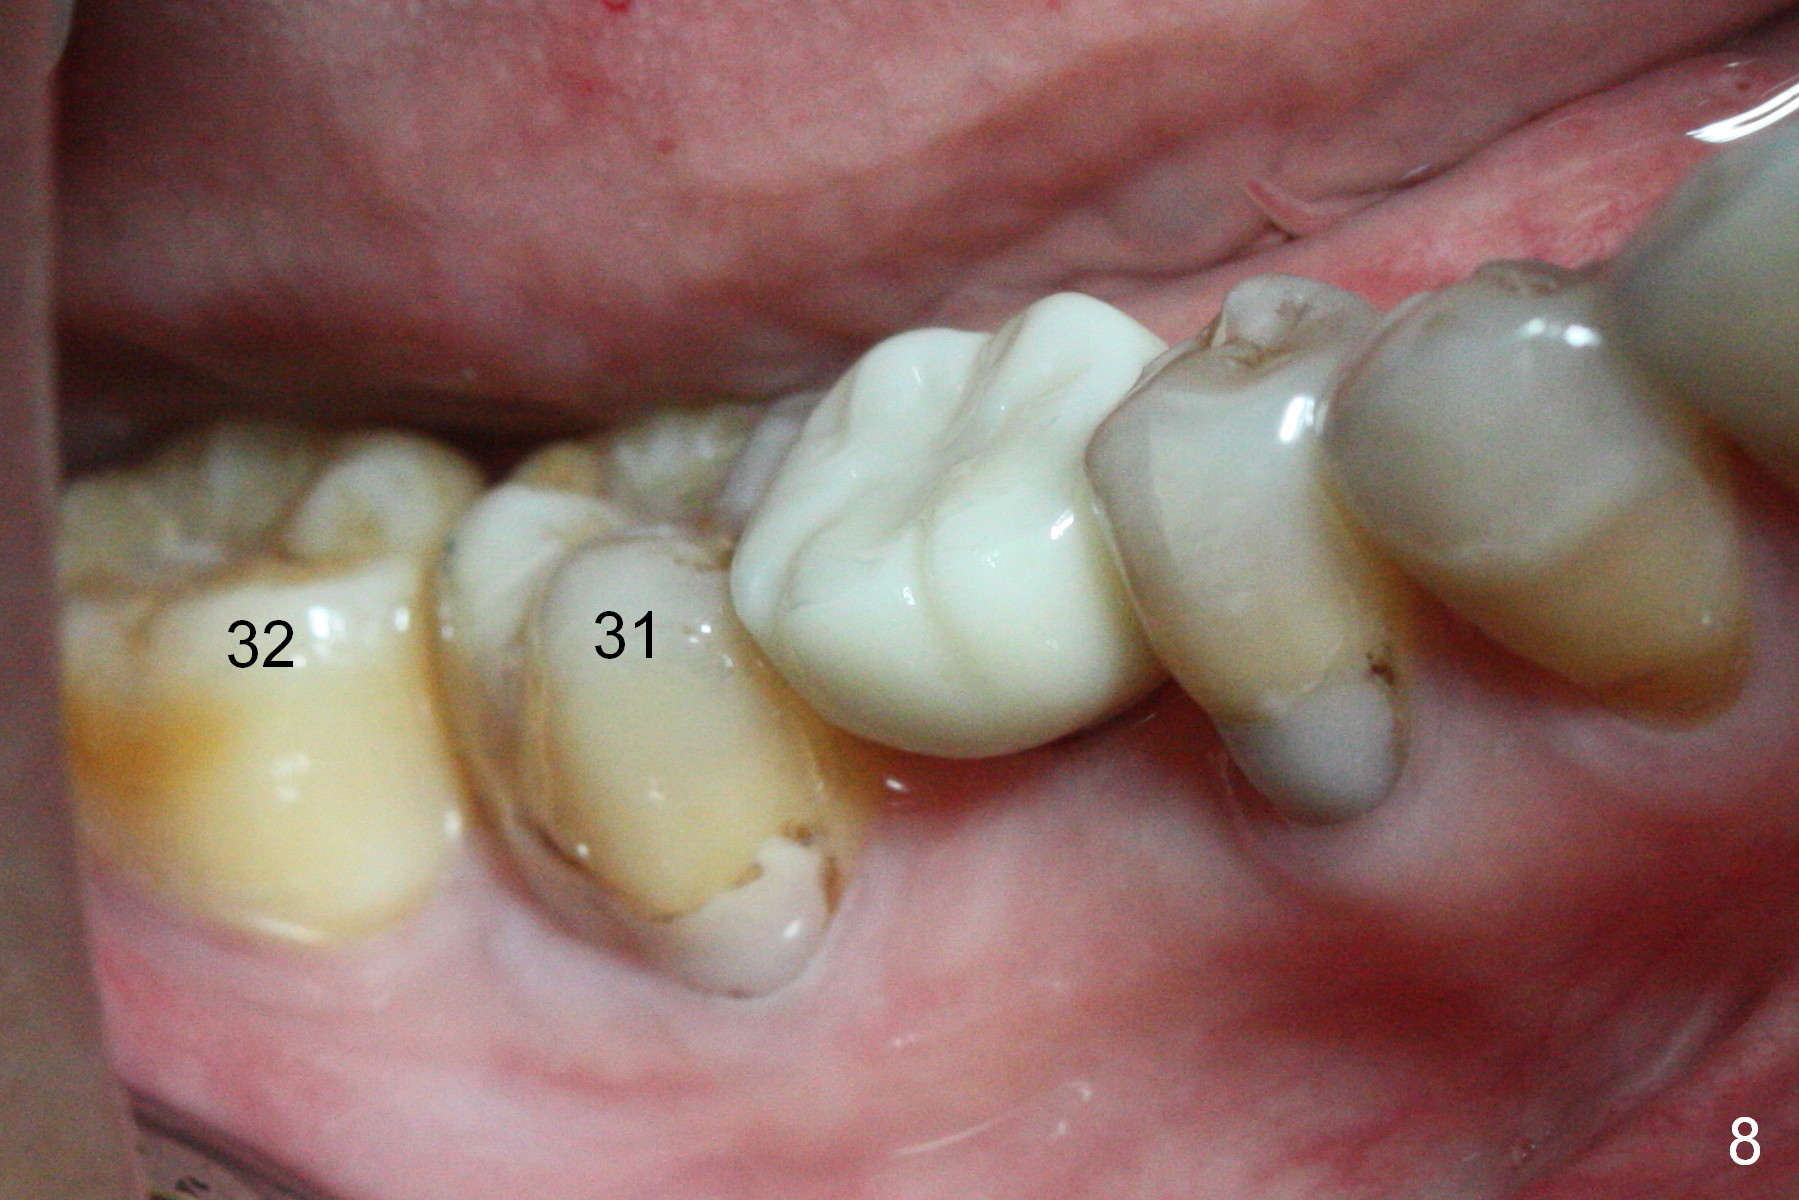

Before crown cementation, the ridge looks wider (Fig.7 *) than preop. There is no diastema between #31 and 32 (Fig.8, 17 days post cementation). The patient is pleased with less food impaction. The total treatment (including ortho) is 16 months. It appears that distalization of #29 is not effective to gain the bone width. In fact simultaneous GBR with implant placement is much more efficient. There is no bone loss 3 months post cementation (Fig.9). The gingiva looks healthy 10 months post cementation (Fig.10). The implant crown is functioning 1 year 9 months post cementation (Fig.11) and 3 years 7 months post cementation (Fig.12).